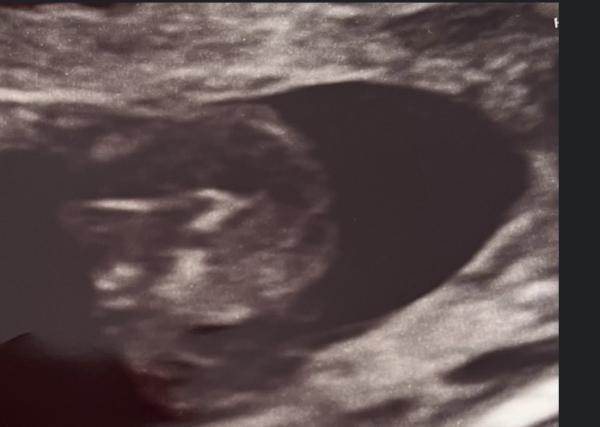

Ich würde tatsächlich sagen, dass es für mich nach einem Babyboy aussieht!  Die meisten verwechseln die drei Linien. Hab mal zwei Bilder im Internet rausgesucht die beide um ca. 20te Woche gewesen sind.  Beim ersten Bild packe ich mal den Jungen rein, beim zweiten das Mädchen. Beide haben drei Linien aber man sieht den kleinen Jungen. Beim Mädchen die Schamlippen Aufteilung.  Bei uns sah es aber echt ungelogen aus wie beim Mädchen. Kann mir bis heute keiner erklären, warum es so war 😄  Aber gut, ab der 25ten woche war aber sofort auf einen Blick zu erkennen was der kleine so zwischen den Beinen hat 😄😄😄